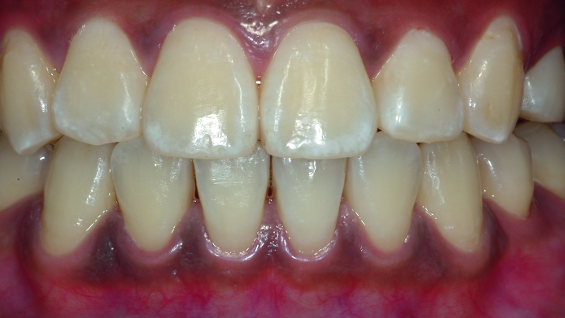

Laser peeling of mucosa between 31 and 41 was noted during photograph taking at one day post-op review (Figs. 10 and 11). The three day post-op photo taken by the patient showed that the laser peel disappeared with new gingival mucosa formation (Fig. 12). Two weeks post-op showed complete recovery of the gingival mucosa without melanin pigmentation (Fig. 13).